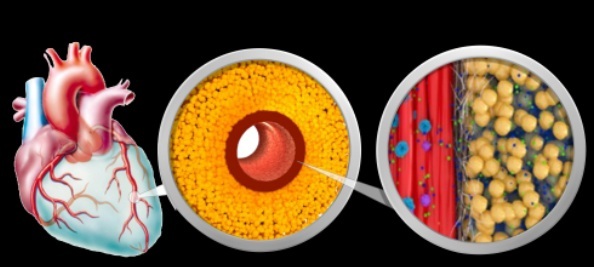

Bei uns finden Sie umfassende Angebote und Untersuchungen, die das Ziel haben, Herz- und Kreislauferkrankungen frühzeitig zu erkennen und Ihnen bei Bedarf mit Erfahrung und Expertenwissen entgegenzuwirken.